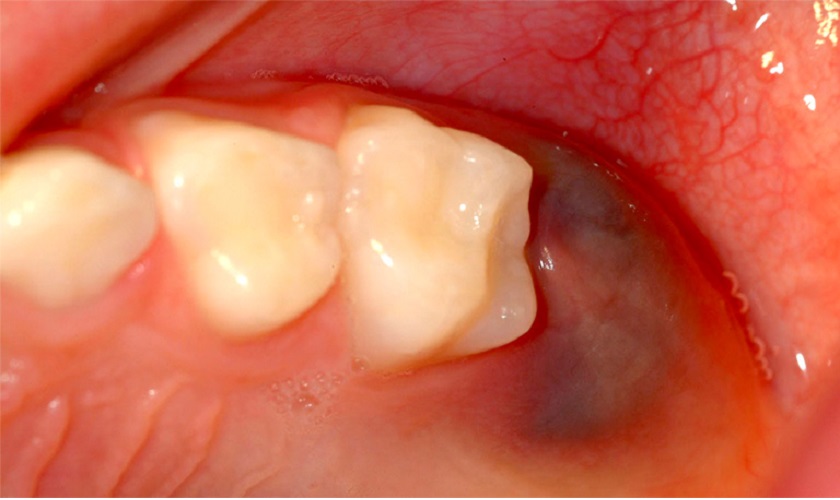

Nha khoa SV quận 3 điều trị viêm lợi trùm uy tín, minh bạch

Nha khoa SV quận 3 là một trong những địa chỉ uy tín hàng đầu tại quận 3 trong việc điều trị viêm lợi trùm. Với đội ngũ bác sĩ chuyên môn cao và nhiều năm kinh nghiệm trong lĩnh vực nha khoa, Nha khoa SV cam kết mang đến dịch vụ chăm sóc sức khỏe răng miệng hiệu quả và an toàn.

Khi đến với Nha khoa SV quận 3 , khách hàng sẽ được thăm khám kỹ lưỡng để xác định mức độ viêm nhiễm và tình trạng răng miệng. Bác sĩ sẽ thực hiện các bước cần thiết như làm sạch khu vực bị viêm, loại bỏ mảng bám và vi khuẩn, giúp giảm đau và sưng tấy. Trong trường hợp cần thiết, bác sĩ có thể chỉ định điều trị bằng thuốc kháng sinh để ngăn ngừa nhiễm trùng và giảm triệu chứng.